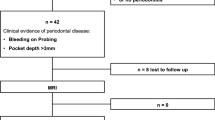

Patients with clinical evidence of periodontal disease who presented at the Department of Periodontology, Ludwig-Maximilians-University Munich, were enrolled prospectively between March 2018 and April 2019. In total, 232 teeth of 37 patients (mean age 62 ± 13.9 years, 18 women) were assessed. All patients were clinically evaluated by dentists. Clinical findings were not available to the MRI examiners, nor were the results of MRI available to clinical examiners.

In total, 232 teeth of 37 patients (mean age 62 ± 13.9 years, 18 women) were assessed. Of those, 84 teeth (36%) have been endodontically treated and 148 teeth (64%) have been included without prior treatment. In 174 cases (75%), a reactive bone edema was detected on MRI by both raters (κ 1.00, 95% confidence interval 1.00–1.00) with 69 cases (30%) showing a corresponding radiolucency on OPT (Figs. 1 and 2). In none of the cases, a radiolucency was detected on the OPT without a related bone edema on MRI.